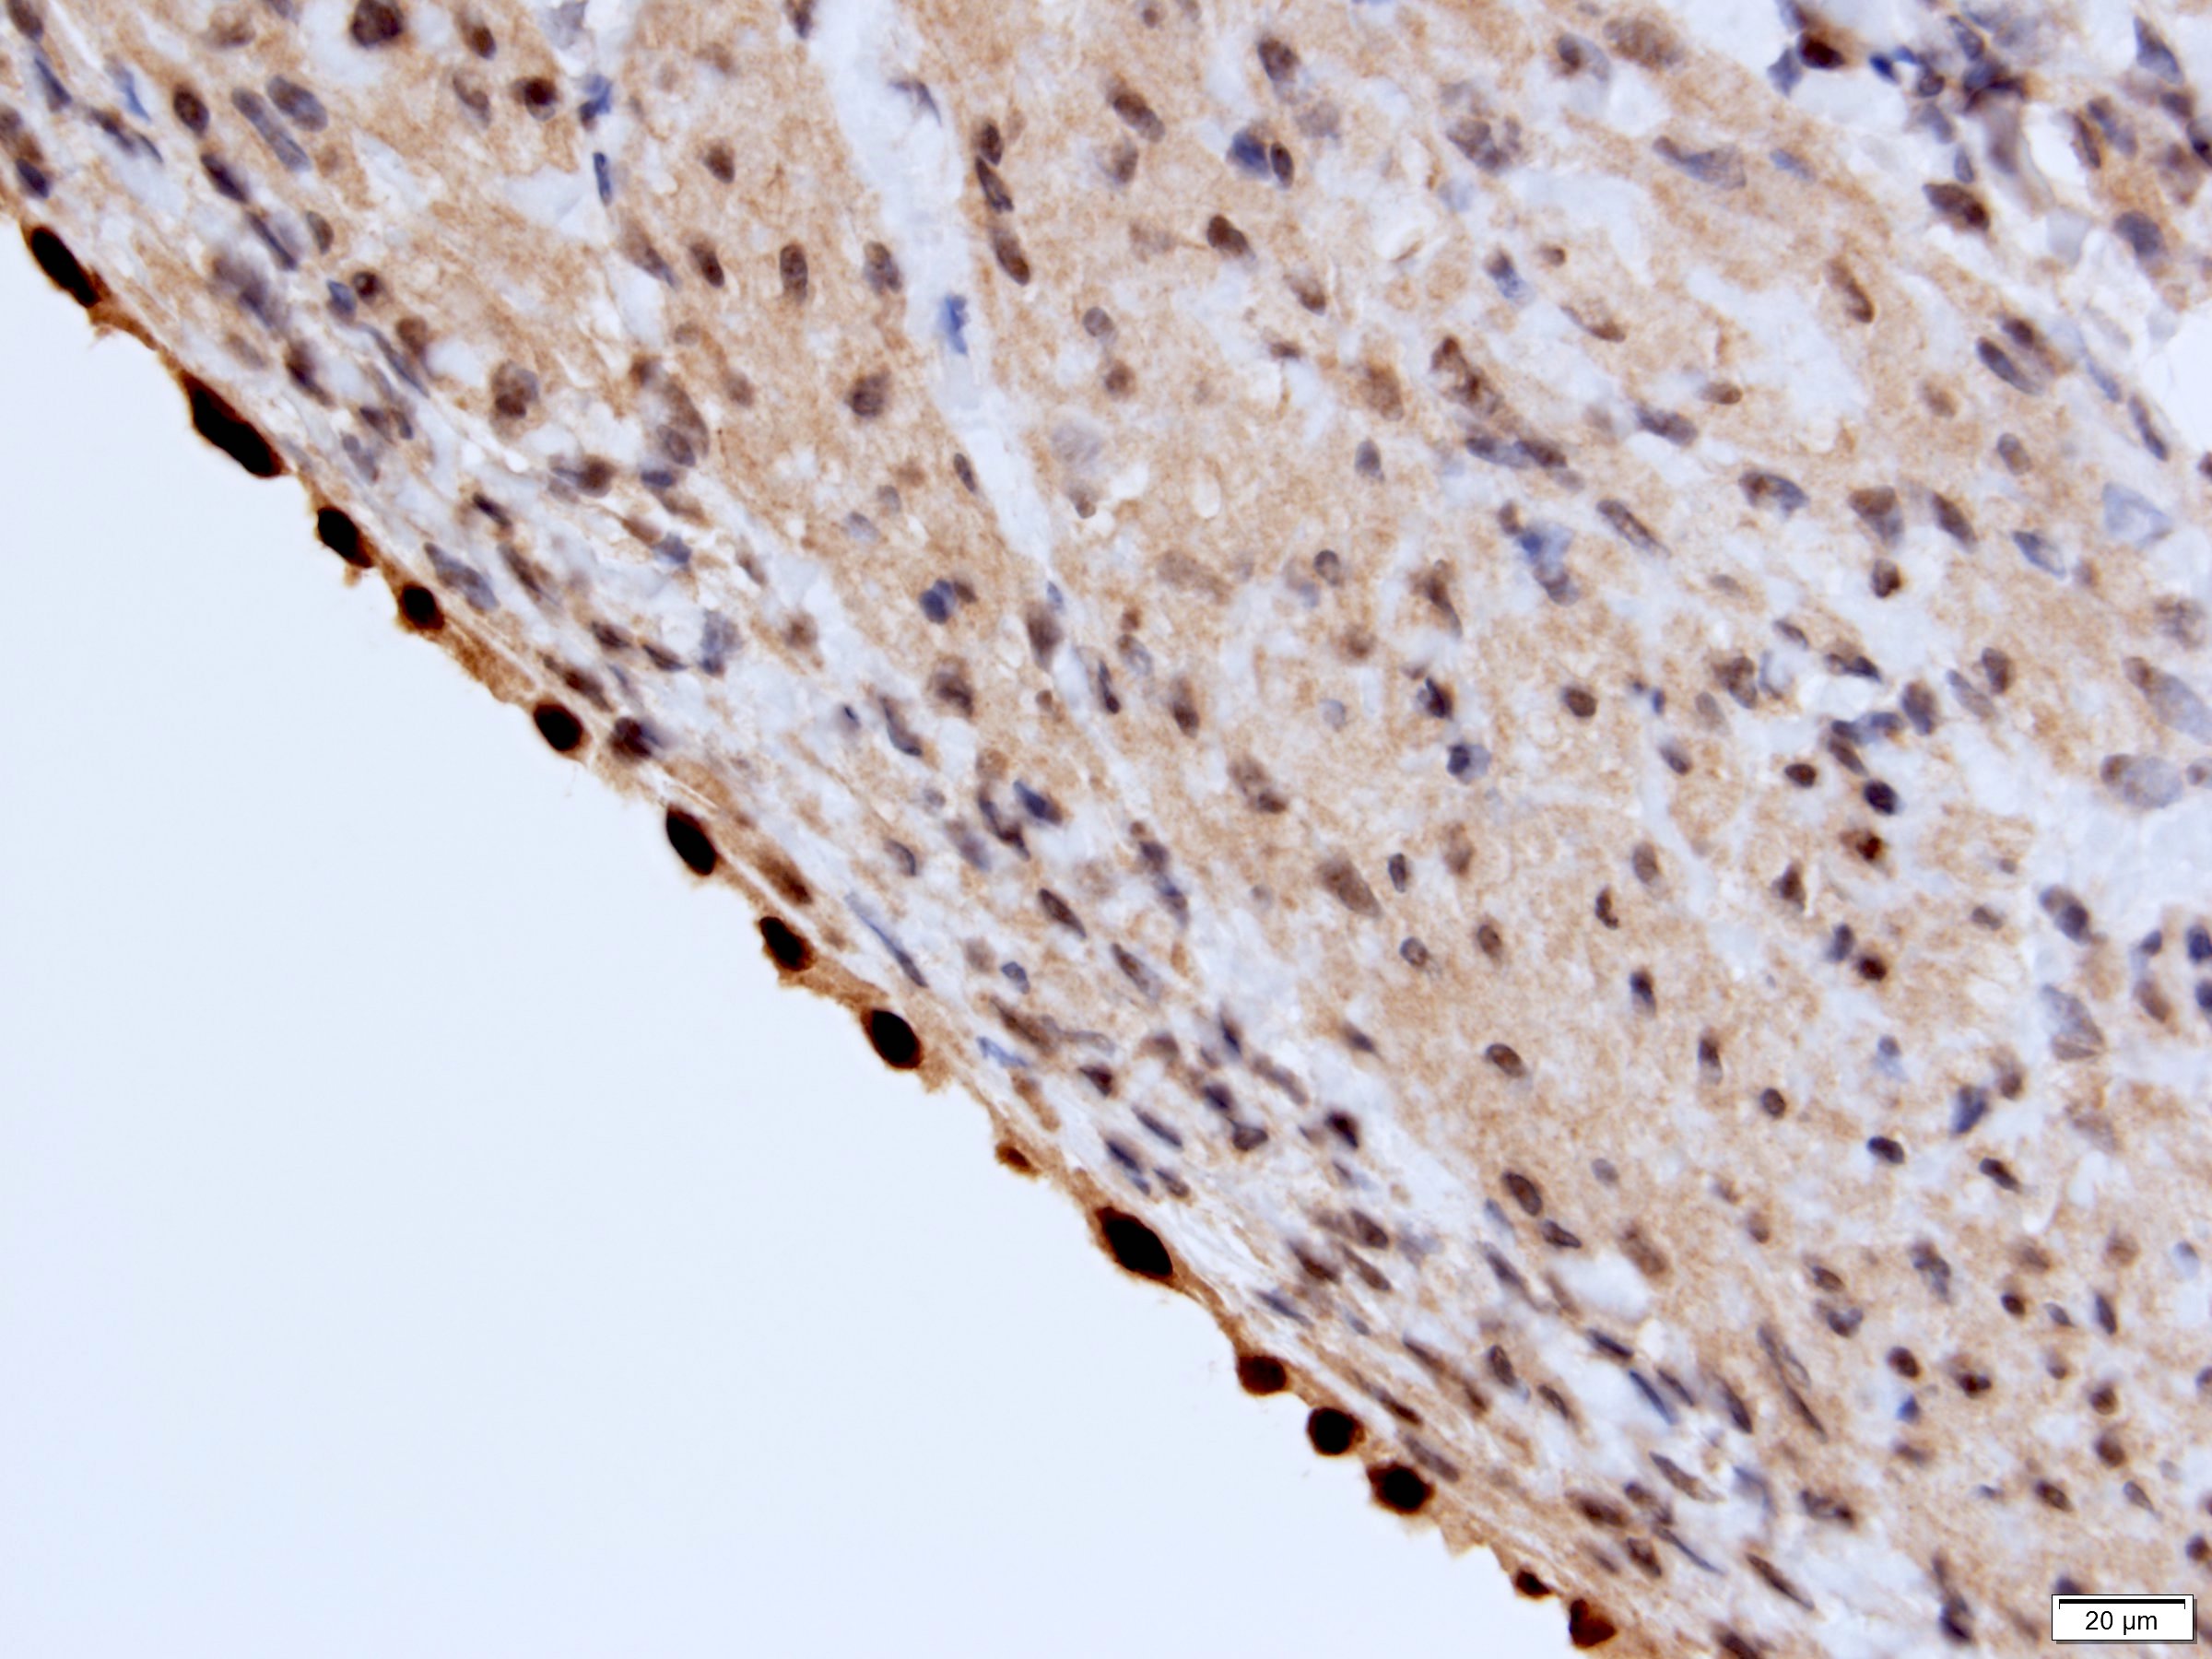

Microscopic (histologic) description

- Many with at least a partial pseudocapsule

- Entirely composed of cysts separated by septa (Semin Diagn Pathol 1998;15:2, Arch Pathol Lab Med 2004;128:1404, Am J Surg Pathol 2007;31:489, Eur Urol 2008;54:1237, Am J Surg Pathol 2016;40:1591)

- Stroma:

- Hypocellular to hypercellular

- Collagenous and fibrous to edematous and myxoid

- Areas of hyalinized stroma with contours resembling ovarian corpora albicantia

- Spindle cells; closely packed areas resemble ovarian stroma

- Cellular foci embedded with epithelial elements ranging from handful of cells with no lumen to tiny cysts with pinpoint lumens and to slightly larger cysts

- Steroidogenic cells: small clusters of polygonal cells with amphophilic cytoplasm and round nuclei, frequently around epithelial component

- Calcifications, multinucleated giant cells, foamy or hemosiderin laden macrophages and focal chronic inflammation

- Epithelium:

- Cells lining cysts

- Mostly arranged in single layer with various morphology: flat, cuboidal, hobnail, clear cell

- Rarely, foci of blunt and delicate papillae or foci of multiple layers of epithelium

- Minimal cytologic atypia

- Rare necrosis, no mitosis

Positive stains

- Stroma:

- SMA: strong and diffuse, 95% (Am J Surg Pathol 2016;40:1591, Arch Pathol Lab Med 2004;128:1404, Arch Pathol Lab Med 2006;130:80)

- Desmin and caldesmon: more variable, 42% and 60%, respectively (Am J Surg Pathol 2016;40:1591, Arch Pathol Lab Med 2004;128:1404)

- ER and PR, 50% and 95%, respectively (Am J Surg Pathol 2016;40:1591, Arch Pathol Lab Med 2004;128:1404, Arch Pathol Lab Med 2006;130:80, Am J Surg Pathol 2007;31:489)

- CD10: mainly in spindle cells around epithelial elements, 81% (Am J Surg Pathol 2016;40:1591, Arch Pathol Lab Med 2004;128:1404, Am J Surg Pathol 2007;31:489)

- FOXL2: in ovarian type stroma, 90% (Hum Pathol 2014;45:1010)

A 6 cm predominantly well circumscribed, multicystic mass was incidentally found in a 55 year old woman. Sections of the partial nephrectomy showed the above histologic features. The stromal component is positive for ER and PR (shown above). What is the likely diagnosis?